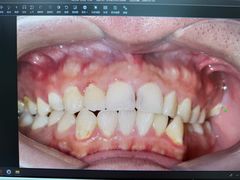

• 牙博士口腔品牌连锁(杨浦店)

• -牙博士口腔品牌连锁(杨浦店)

wenwenqing | 25-05-31